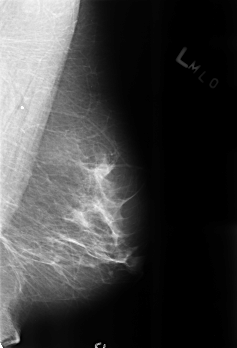

B_3207_1.LEFT_MLO

LEFT_MLO LINES 4512 PIXELS_PER_LINE 3072 BITS_PER_PIXEL 12 RESOLUTION 50 NON_OVERLAY